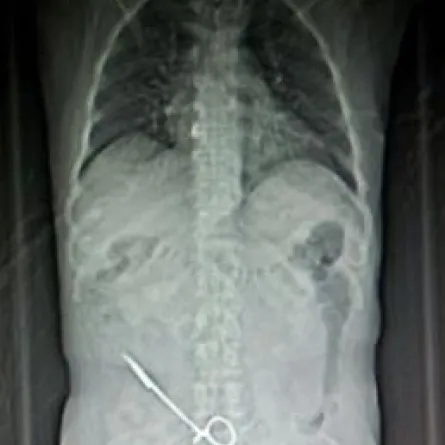

وذكرت صحيفة "عكاظ" أن المريض، الذي بث صور أشعة تبين وجود المقص داخل البطن، شعر بألم حاد في البطن، وحضر لطبيبه الذي طلب منه إجراء أشعة، وتبين وجود مقص العملية السابقة منسياً في بطن المريض، حيث قام الطبيب فوراً بإجراء عملية أخرى واستخراجه.